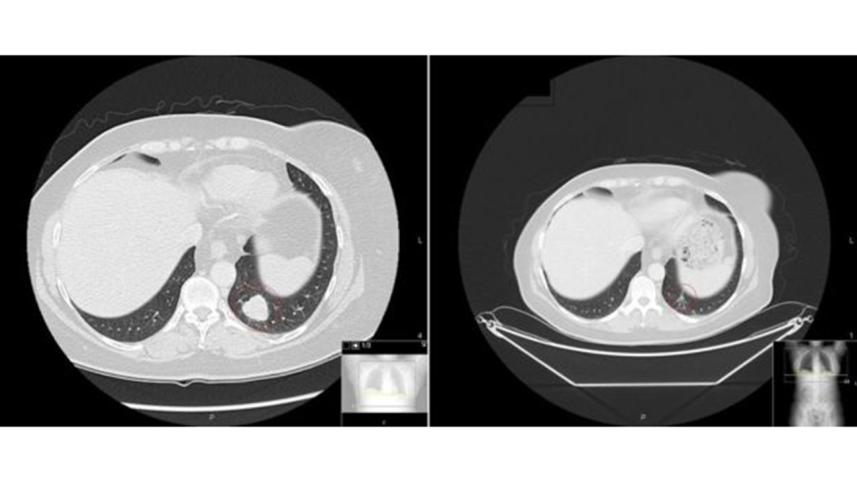

Melanoma before and after therapy. Photo: BBC/ Royal Marsden

The trial showed the survival rate after two years for ipilimumab alone was 53% and no patient's tumours had completely disappeared.

The equivalent figures for combination therapy were 69% and 22%.